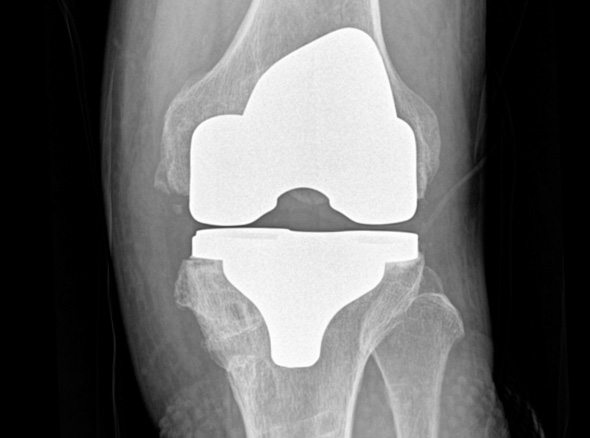

손상된 무릎 뼈를 제거하고, 그 부위에 특수 소재의 금속 재질로 구성된 인공관절을 삽입하는 수술을 시행할 수 있습니다.

관절연골이 망가져 쓸 수 없을 때 관절기능 회복을 위해 시행하며, 인공관절의 수명은 20~30년 정도 됩니다.

세계적인 의료기기 기업 스트라이커(Stryker)사의 특화된 임플란트를 사용합니다.

정밀한 설계, 내구성, 생체 적합성 등의 장점을 두루 갖추어 전 세계적으로 가장 많이 사용되고 있습니다.